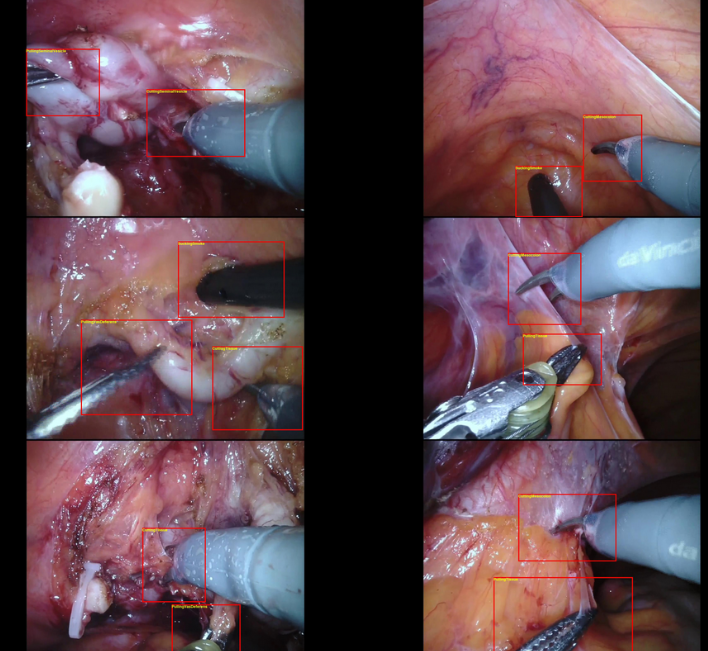

SARAS-MESAD

| SARAS-MESAD | 24种动作 | 静态背景动作识别 | 内窥镜 | 4(真实手术)+5(模拟手术) | CC BY-NC-SA 4.0 |

| SARAS-ESAD | 21种手术动作 | 静态背景动作识别 | 内窥镜 | 22,601(训练)+4,574(测试) | 图片 | BB | CC BY-NC-SA |